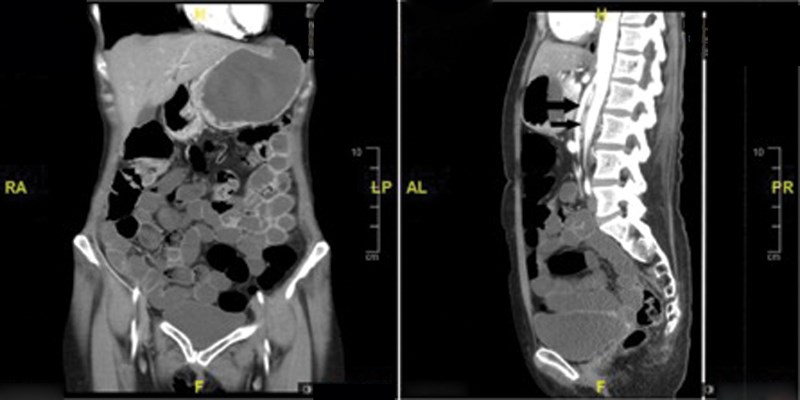

Superior mesenteric artery syndrome is a rare cause of intestinal obstruction. The condition results from compression of the duodenum between the aorta and the superior mesenteric artery, which causes an impairment of gastric emptying and associated chronic symptoms. There is a need to objectively assess the severity of gastric-emptying disorder in these patients post-treatment to assess the efficacy of the conservative or surgical management. We report here a case of a patient where the radionuclide gastric-emptying study was crucial in monitoring the effectiveness of surgical management of this syndrome.